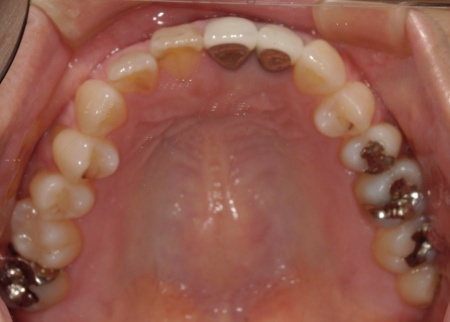

拝見したところ、上下前歯には金属製の土台「メタルコア」を使用した被せ物(クラウン)が装着されており、被せ物と歯茎の境目付近が黒くなっていました。

被せ物の土台がメタルコアの場合、以下のような理由から歯茎との境目が黒く見えることがあります。

・メタルコアから溶け出した金属成分が歯茎に沈着し、黒色〜青黒色に見えることがある

・歯茎が薄い方の場合、土台の金属色が透けて暗く見えることがある

・土台を作製したり形を整えたりする時に生じた金属の細かな粉が歯茎に入り込み、黒い点として見えることがある(メタルタトゥー)

そのため、黒ずみの原因であるメタルコアを除去する治療が必要でした。

また、保険適用の白い詰め物(コンポジットレジン)が充填されている部分には変色が見られます。ご自身の歯、被せ物、コンポジットレジン、それぞれの色調が異なっていることで審美性に影響が出ているため、上下前歯(合計12本)の被せ物と詰め物を新しくする必要があると診断しました。